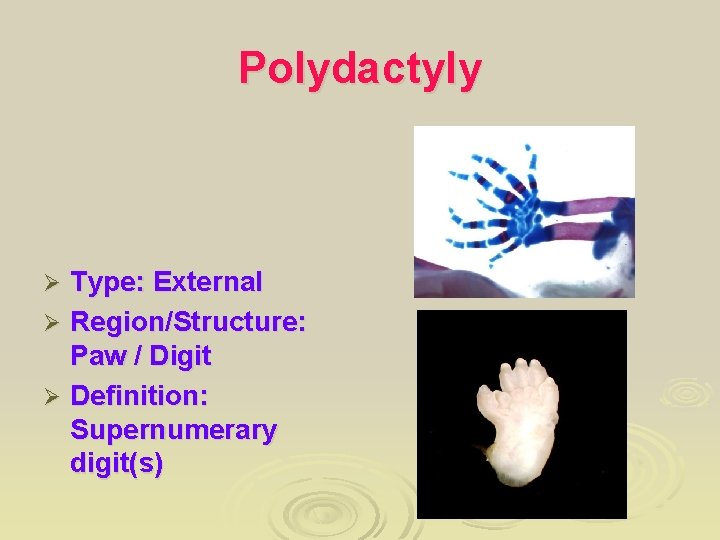

Limb anomaly Ø A) brachydactyly Ø B) hypoplasia of the thumb Ø C) polydactyly (fingers) Ø D) polydactyly (toes) Ø E) Partial duplication of the foot Ø F) Partial duplication of the thumb

Polydactyly Showing partial duplication of the right foot & toes Ø Supernumerary digits which is incompletely formed and lack of muscular development Ø

Polydactyly Type: External Ø Region/Structure: Paw / Digit Ø Definition: Supernumerary digit(s) Ø